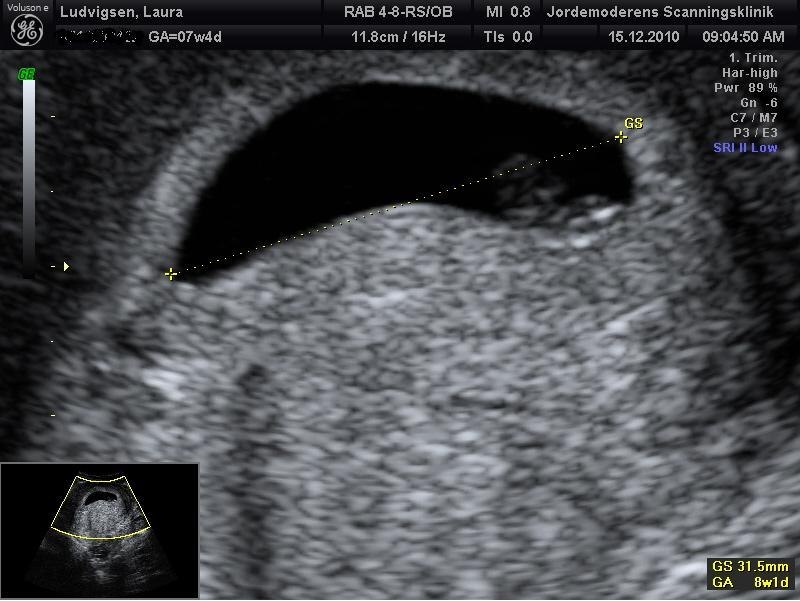

uh meget fint, har selv os overvejet at betale for en scanning bare for at få det helt bekræftet... Altså lægen har bekræftet det, men .... føler bare ikke det er nok. ku godt være man sku gøre det samme og få lavet en scanning